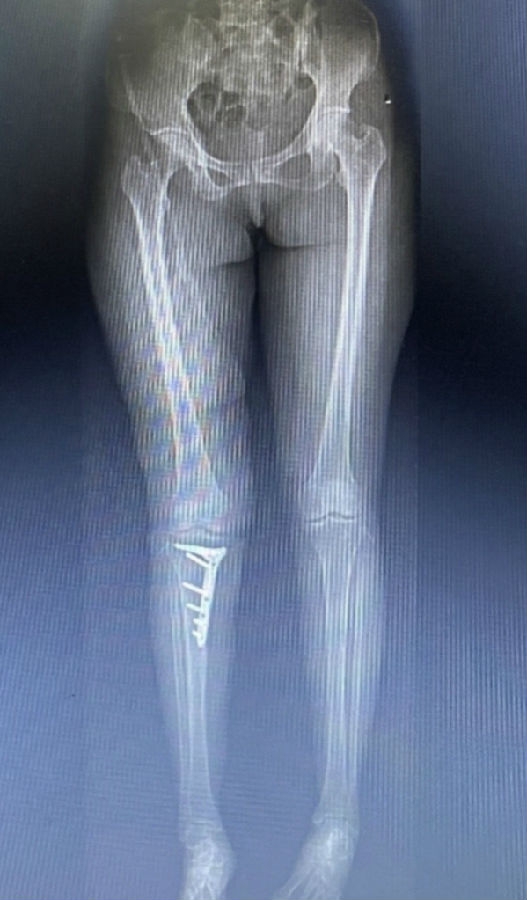

术后影像

因此,术中用关节镜在髁间窝和髌上囊分别取出了两枚游离体,术中也验证了MR显示的外侧关节面水肿区不是位于外侧间室的负重区,关节镜下外侧软骨为全层软骨,软骨退变区位于股骨滑车沟外侧近潮线处,内侧软骨磨损,部分裸露。故在内侧清理后加做HTO,将力线调整至55%。术者相信这是最利于患者的治疗选择。